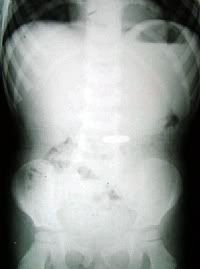

Loli-pop Mesaj tarihi: Temmuz 22, 2005 Mesaj tarihi: Temmuz 22, 2005 BURSA (İHA) - Bursa'nın İnegöl İlçesi'nde annesinin harçlık olarak verdiği demir 1 milyon lirayı ağzında oynarken yutan 1 çocuk, hastanelik oldu. İlçeye bağlı Alanyurt Beldesi'nde meydana gelen olayda, 4 yaşındaki F.E.G., annesi F.G.'nin verdiği demir 1 milyon lirayı alarak bakkala gitmek için merdivenlerden inerken, parayı ağzına götürdü. Ağzındaki parayla oynarken birden yutan küçük F.E.G., tekrar eve dönerek, annesine durumu anlattı. Devlet Hastanesi'ne kaldırılan çocuğun çekilen röntgen filminde, midesinde demir bir nesne olduğu tespit edildi. Müşahede altına alınan çocuğun gerekirse ameliyat edileceği öğrenildi.[signature][hline]- Aya inemiyoruz? - Neden, modül mü bozuldu? - Yok, Kültür Bakanlığı sit alanı ilan etmiş, bilet almamız lazımmış...[Bu mesaj Loli-pop tarafından 23 Temmuz 2005 00:49 tarihinde değiştirilmiştir]